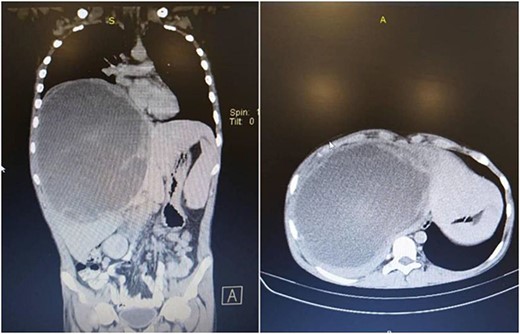

Right extended hepatectomy (the 4a, 4b, 5, 6, 7, 8 segments) with cholecystectomy were performed. The hepatic lobe weighed 1700 g and measured 190 × 170 × 150 mm (Fig. 4). Sections showed somewhat well-defined total necrotic mass measuring ~14 cm in the largest dimension, not reaching the hepatic capsule surface. Multiple sections were submitted for histologic examination, lymph node measuring 1.5 cm. The entire specimen was embedded for histologic examination, the gallbladder measured 7 × 4 cm and showed 0.7 cm black stone, and no masses were seen.

The histologic examination of the excised lesion revealed an entirely necrotic liver tissue mass due to a total burnt-out tumor with excellent treatment response. No viable tumor cells were seen. The remaining hepatic tissue showed no significant pathologic changes, and all surgical margins were free of neoplastic changes. The hepatic hilar lymph node was free of tumor (0/1) and mild chronic cholecystitis and cholelithiasis were seen in the gallbladder.